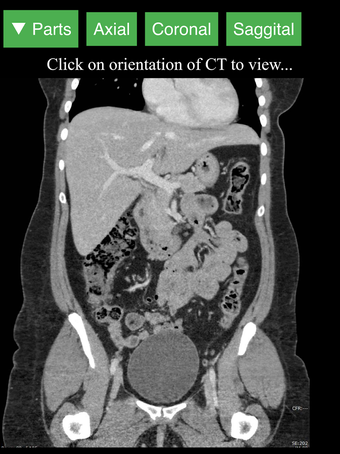

Radyoloji BT Görüntüleyicisi, doktorlar, tıp öğrencileri, radyoloji teknisyenleri ve diğer sağlık profesyonellerinin insan vücudu ve anatomisi hakkında daha fazla bilgi edinmelerine yardımcı olan faydalı bir araçtır. Uygulama, en önemli insan vücut parçalarının detaylı kesit çizimlerini içerir. Ayrıca, anatomiyi daha iyi görmek için görüntü etrafında döndürme, yakınlaştırma ve kamera hareket ettirme imkanı sunan etkileşimli bir 3D model içerir.

İnsan vücudu hakkında daha fazla bilgi edinmenize yardımcı olacak bir araç arıyorsanız, Radyoloji BT Görüntüleyicisi harika bir seçimdir. Detaylı çizimler ve etkileşimli bir 3D model içerir.